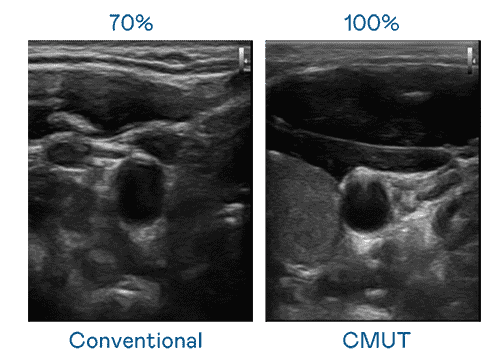

CMUT 技术是一种用电容式微机电元件来产生超音波讯号的技术。。与传统 PZT 压电式技术相比,,,CMUT 频宽增加 30%,,更宽频的超音波讯号让影像解析度大幅提升,,,是实现高影像品质医疗超音波扫描、、促进精准医疗发展的关键技术。。。。

超音波影像的解析度高低,,首先取决于探头能发出的讯号频宽。。。。尊龙z6 CMUT 可提供高清晰的超音波讯号,,,提供高频宽、、、高灵敏度、、影像纹理细节更高的超音波影像,,,协助医护人员缩短影像判读时间及利用精准的医疗影像进行诊断。。。